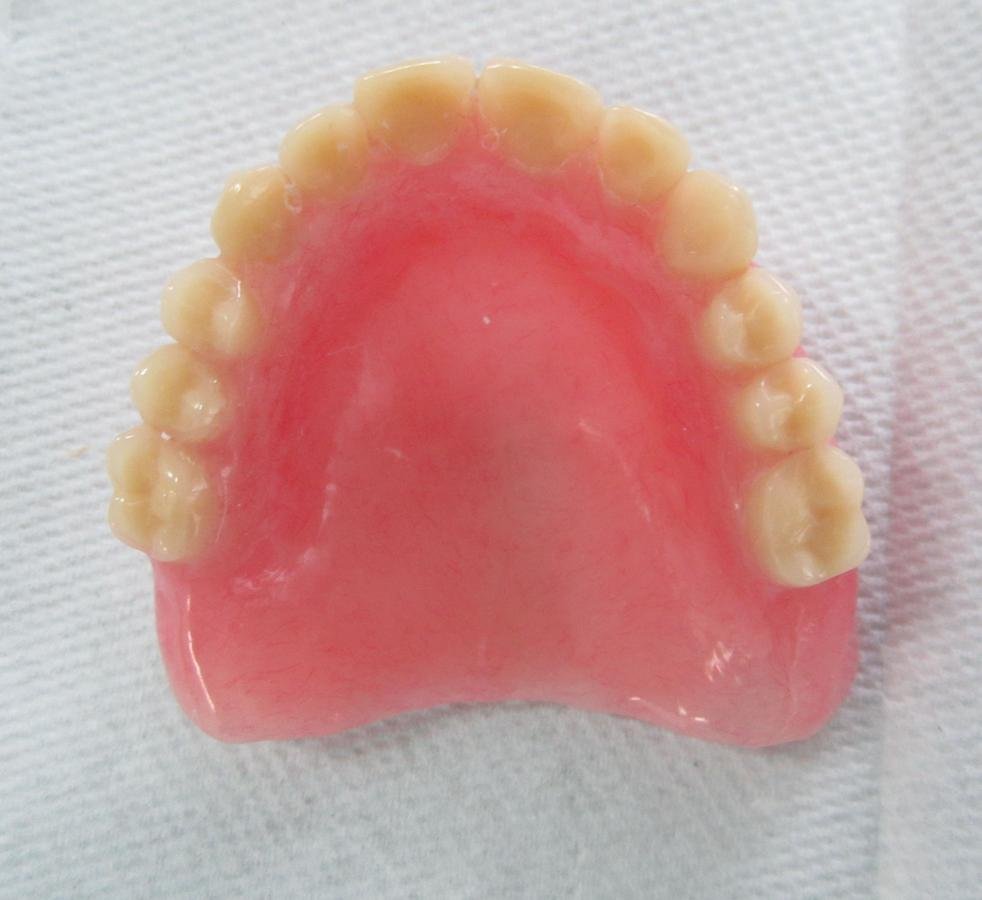

Elaboración de prótesis total superior e inferior

bajo técnica de inyección

con resina fotopolimerizable -Eclipse-

ECLIPSE

Resina fotopolimerizable

Libre de monómeros metílicos, etílicos, propílicos o butílicos

Tres componentes: material de base, de montaje y de contornos.

Colores: rosa veteado, rosa claro veteado, rosa-rojo veteado e incoloro

TRATAMIENTO FINAL

Prótesis total superior e inferior elaboradas con Eclipse